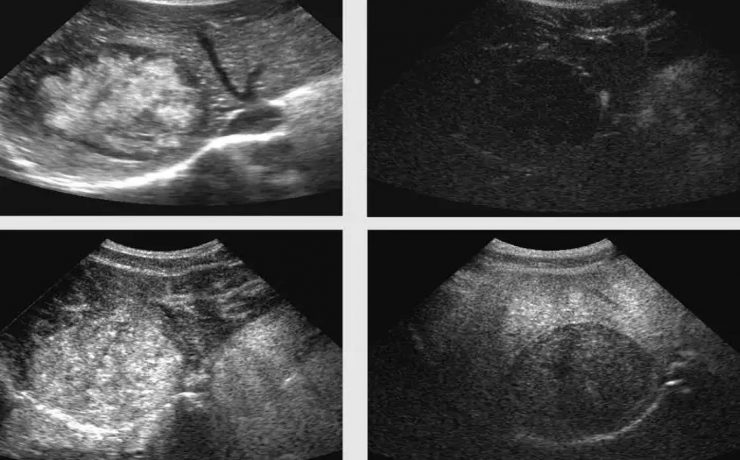

El síndrome de Rokitansky, es la anomalía más grave del tracto reproductivo femenino. Consiste en la ausencia congénita de vagina y útero ausente o rudimentario, como consecuencia de la falla en el desarrollo Mûlleriano de la vagina y el útero. Este síndrome fue descrito por Rokitansky en 1838. Es la